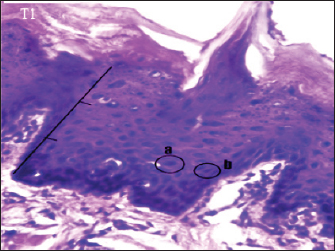

The histopathology of the tongue epithelium of rats in the T1 group revealed dysplastic cells. Cell form and size variations (anisocytosis and pleomorphism) and irregular epithelial stratification due to nuclear shape and size differences. The ratio of nuclei to cytoplasm rises, and hyperchromatic nuclei are visible. Cell changes affect two-thirds of the thickness of the rat tongue epithelium. Therefore, this is classified as mild dysplasia (Fig. 3).

Fig. 3. Histopathological description of the rat tongue epithelium in the T1 group, microscope at ×400. (a) the ratio between the nucleus and the cytoplasm increases, with a hyperchromatic nucleus; (b) the shape of the nucleus showing anisonucleus.